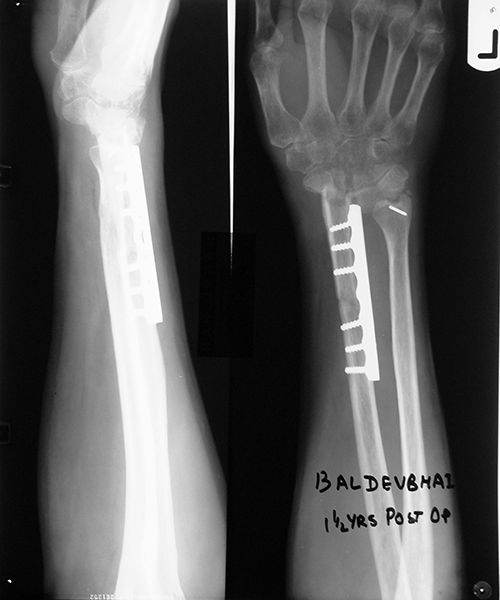

Case:1 GCT L/E Radius

Pre-Op

One and Half month follow up

One and Half year foll

2 years Follow-Up